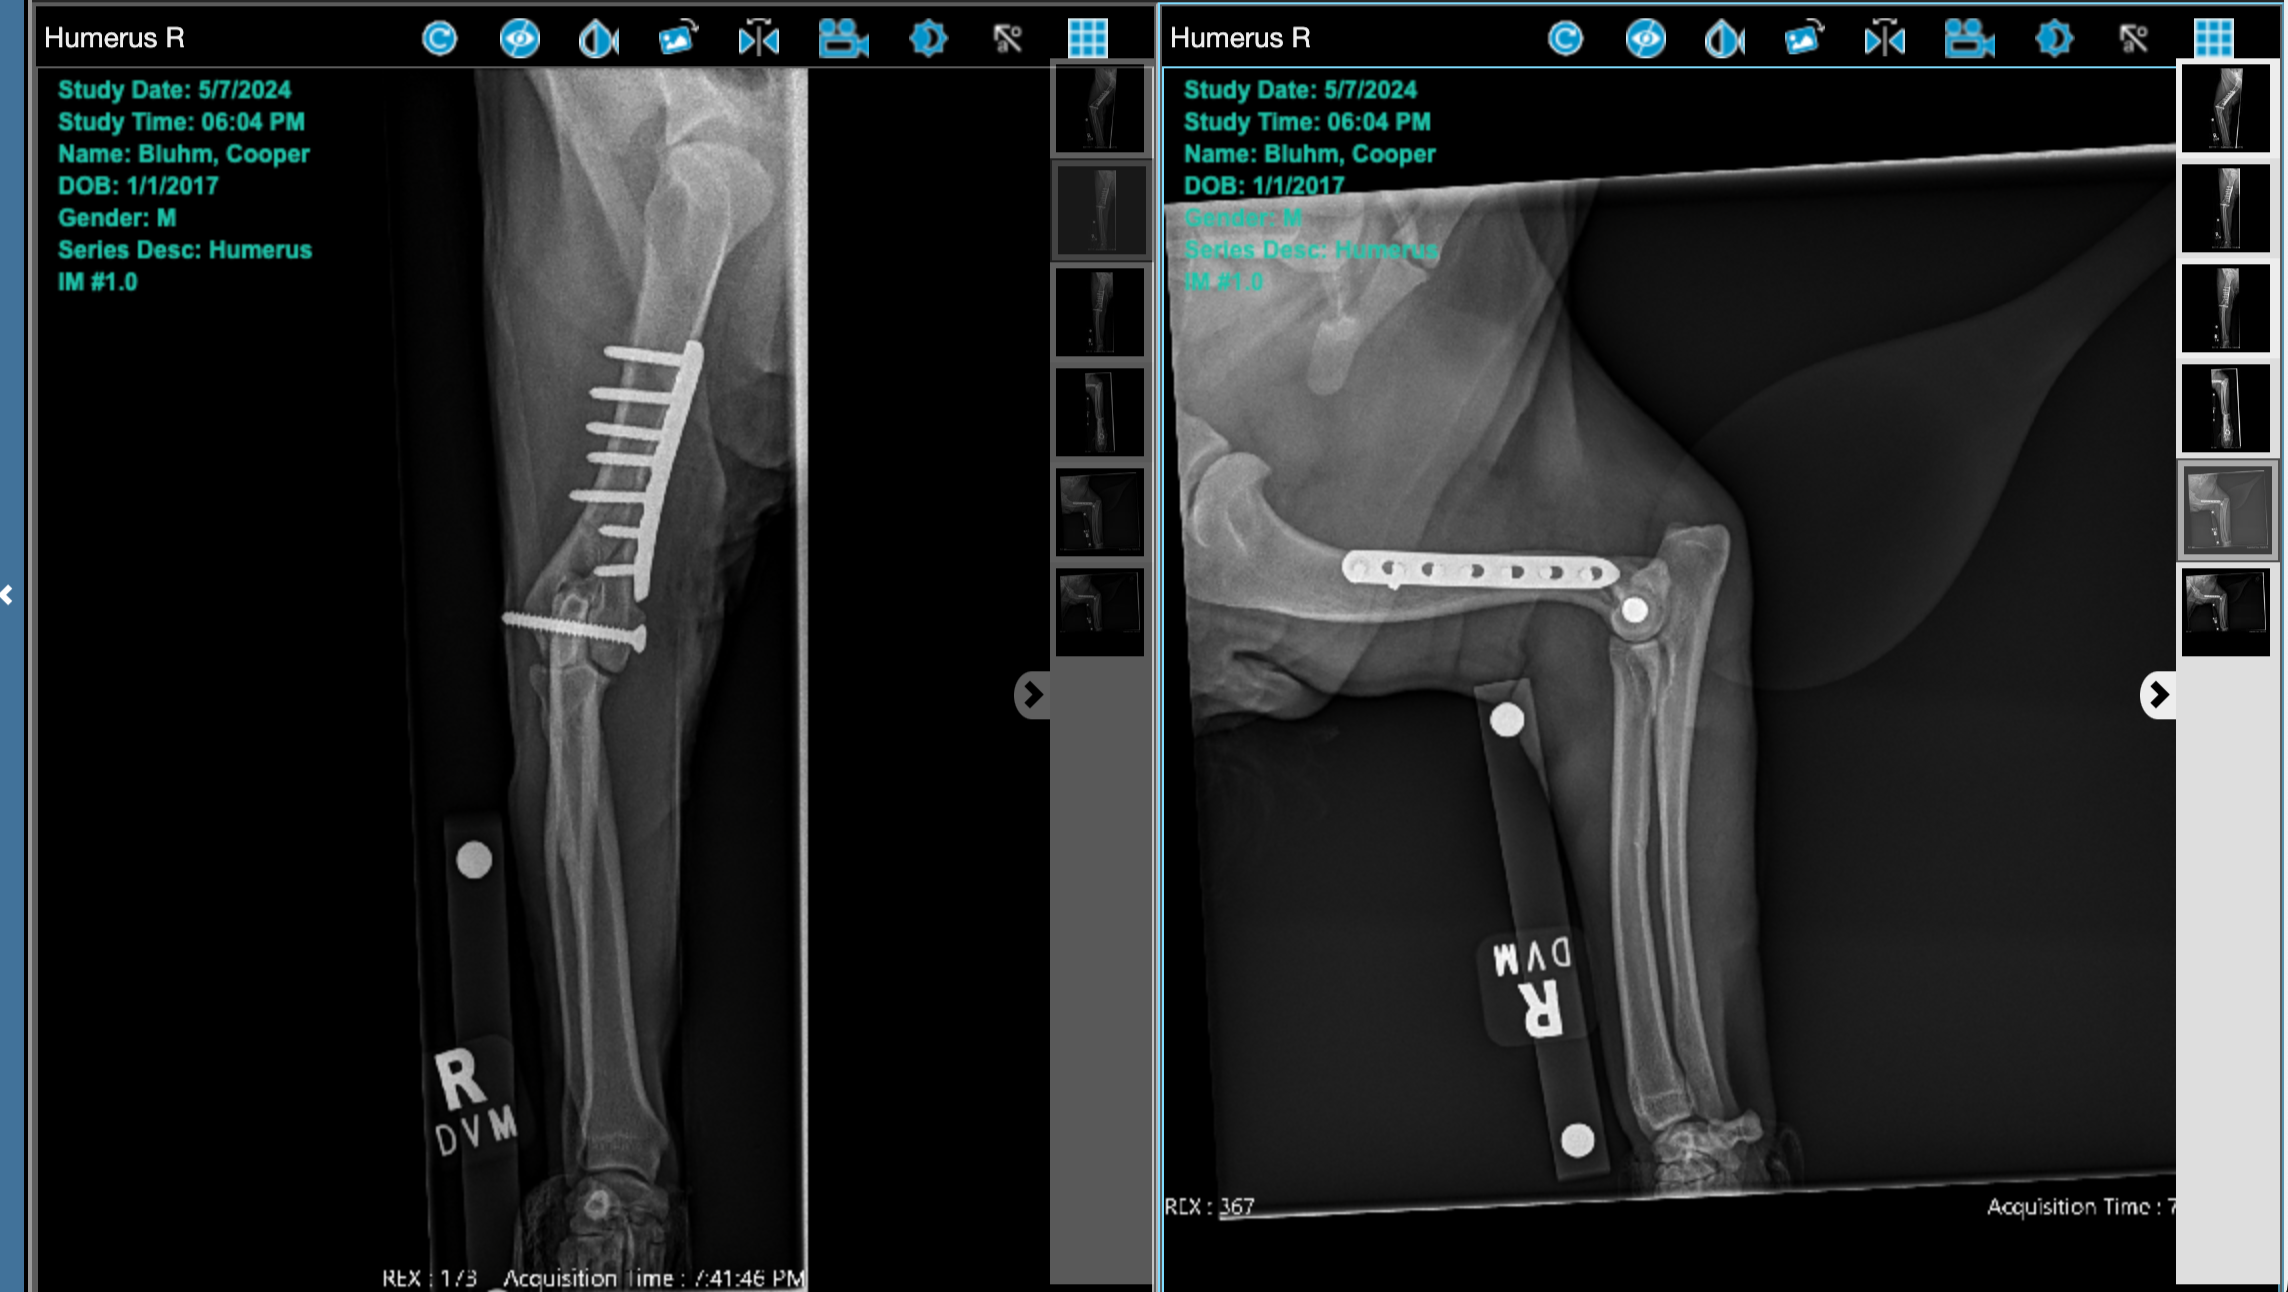

Two weeks after we brought Cooper home, he was sitting in a chair with Mark. As he went to hop down, he landed just right and snapped his humorous. I knew immediately it was broken. It was such a freak accident and the force made no sense to cause such a break, but it was obvious he was in excruciating pain. We rushed him into the vet and got him sedated and xrayed, confirming the break. We immediately got him transferred to OSU Veterinary Small Animal Hospital, and they got him in surgery the very next day.

OSU Vet Hospital advised us that Cooper has IOHC, or Incomplete Ossification of the Humeral Condyle in canines. This means that when he was 8-12 weeks old, his humeral condyle did not fully develop, leaving the joint weaker. Spaniels make up a large representation of canines who have this happen. At least we know why it broke so easily. We’ve checked his other elbow and it doesn’t seem to have the same problem, thankfully. More about this condition here: https://www.veterinary-practice.com/article/incomplete-ossification-of-the-canine-humeral-condyle